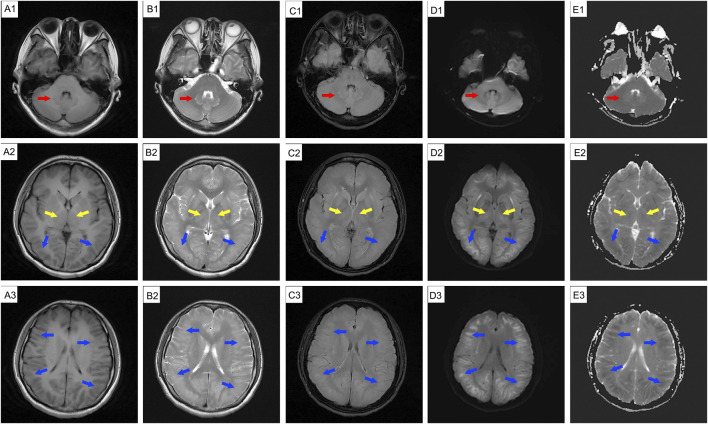

背景:1,2-二氯乙烷是一种常用的工业溶剂。急性或亚急性职业性接触可引起中毒性脑病;然而,脑成像的长期变化并不经常被记录下来。病例介绍:一名39岁女性在涂胶9天后出现头晕和健忘。休息7天后,她的症状明显好转。然而,恢复工作3天后,她返回时出现头晕、头痛和焦虑。脑磁共振成像(MRI)显示小脑齿状核、基底节区和双侧脑白质广泛水肿和弥漫性异常信号。给予丹参酚酸注射液、异甘草酸镁及神经营养治疗。入院两周后,除轻度行走不协调外,患者症状明显改善。异常MRI信号的范围与先前的发现一致。她第二天就出院了。3天后头痛加重。计算机断层扫描显示弥漫性脑水肿。尽管用甘露醇治疗,她的头痛迅速恶化,并伴有恶心、呕吐、高血压、心动过缓和呼吸困难,最终导致昏迷。后续MRI显示与前次扫描相似,只是表观扩散系数(ADC)序列由低信号变为高信号。核磁共振检查后不久,她出现呼吸骤停。不幸的是,由于严重的脑损伤和感染,她在初次入院32天后死亡。结论:职业性暴露于1,2-二氯乙烷可导致中毒性脑病,表现为弥漫性进行性脑水肿。该病例表明,脑成像结果可能并不总是与患者的临床状况相关,因此仔细监测是必不可少的。

Case presentation: A 39-year-old woman developed dizziness and forgetfulness 9 days after performing glue coating. Her symptoms improved significantly after a 7-day break from work. However, after resuming work for 3 days, she returned with dizziness, headache, and anxiety. Brain magnetic resonance imaging (MRI) showed extensive edema and diffuse abnormal signal intensities in the cerebellar dentate nucleus, basal ganglia, and bilateral cerebral white matter. She was treated with salvianolate injection, magnesium isoglycyrrhizinate, and neurotrophic therapy. Two weeks after admission, her symptoms improved significantly, except for mild uncoordinated walking. The range of abnormal MRI signals remained consistent with previous findings. She was discharged the following day. She experienced worsened headache 3 days later. Computed tomography revealed diffuse cerebral edema. Despite treatment with mannitol, her headache rapidly worsened and was accompanied by nausea, vomiting, hypertension, bradycardia, and dyspnea, ultimately leading to unconsciousness. Follow-up MRI showed findings similar to the previous scan, except that the apparent diffusion coefficient (ADC) sequence had changed from hypointense to hyperintense. Shortly after the MRI examination, she experienced respiratory arrest. Unfortunately, she died 32 days after her initial admission due to severe cerebral injury and infection.